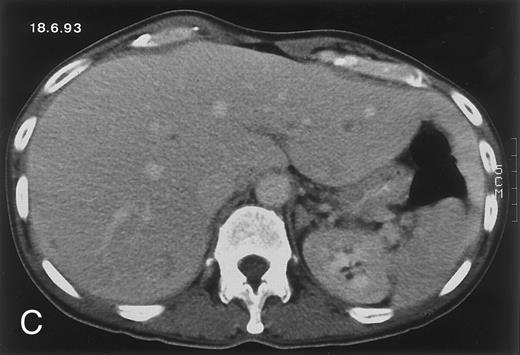

Radiologic evolution in patient A. (A) Postcontrast abdominal CT scan on March 16, 1993 shows multiple small hypodense areas in all segments of the liver, suggestive of hepatic candidiasis. Seven days previously, the patient had recovered from severe neutropenia after the first cycle of chemotherapy for AML. (B) On April 23, 6 days after the neutrophil count had dropped below 500/μL in the second cycle of chemotherapy, there is no evidence of focal lesions on postcontrast CT scan. (C) On June 18, when neutrophils were normalized for 46 days, CT scan again shows multiple small abscesses.